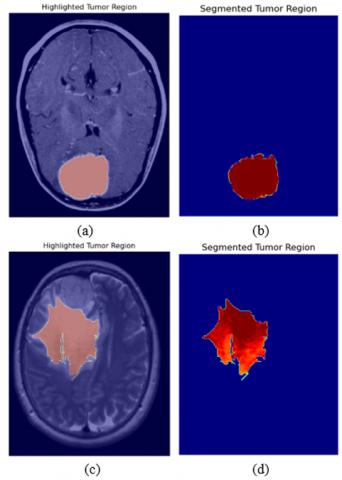

Figure 11. Results of graph-based algorithm for segmentation

Figure 11 shows the successful segmentation results where the algorithm accurately highlighted the tumor region, achieving near-perfect delineation of the tumor boundaries. To further understand the limitations of the technique, Figure 12 consists of MRI images where the technique failed to highlight and segment the tumor region.

Images on which the segmentation performed poorly are shown below where the technique fails to highlight the tumor region.